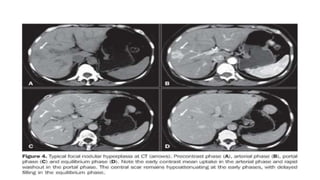

FNH: imaging

• Usually associates several findings

1. Lesion homogeneity, excluding the central scar

2. Slight difference from adjacent liver tissue on pre-contrast US, CT and MRI

3. Strong, homogeneous enhancement on arterial phase CEUS, CT or MRI with

a central vascular supply; becomes isointense to liver tissue on portal venous

and delayed phases

4. Central scar best seen on MRI

5. Lack of capsule with often lobulated contours